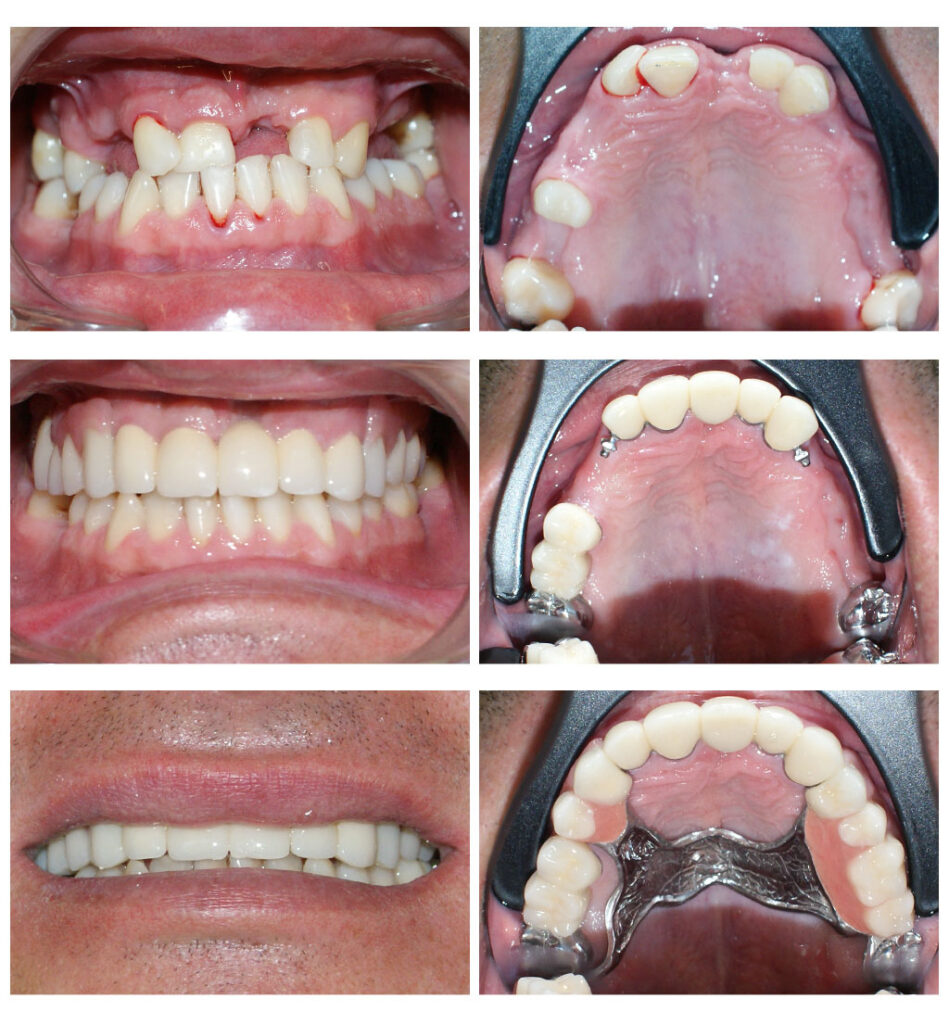

Lucrare fixată pe dinți împreună cu proteză scheletată mobilizabilă = soluția de lux pentru dinți puțini